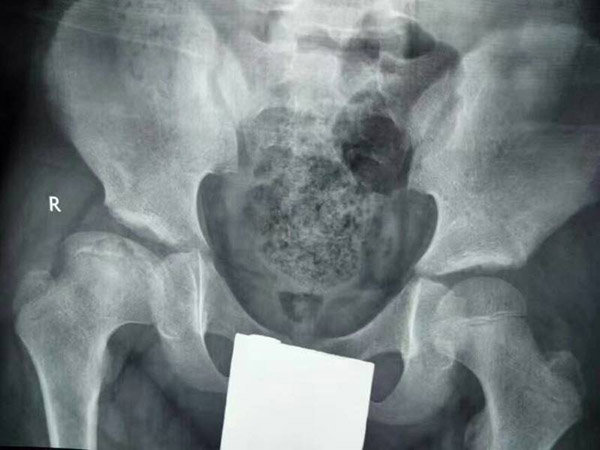

治疗前

治疗中

治疗后